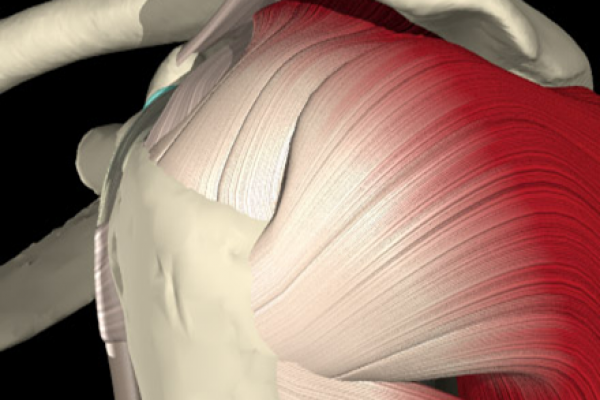

Le complicanze chirurgiche e riabilitative - Osservazione e valutazione clinica del paziente - Valutazione e trattamento delle discinesie scapolari (nuovi concetti) Presentazione casi clinici, valutazione dei pazienti - Discussione sui casi clinici analizzati - Il trattamento chirurgico - Esercizi specifici di rinforzo

Le schede di valutazione - Il recupero della mobilità articolare passiva ed attiva - Parte pratica: Mobilizzazioni passive e tecniche di presa - Valutazione Clinica/funzionale

Le complicanze chirurgiche e riabilitative - Osservazione e valutazione clinica del paziente - Valutazione e trattamento delle discinesie scapolari (nuovi concetti) Presentazione casi clinici, valutazione dei pazienti - Discussione sui casi clinici analizzati - Il trattamento chirurgico - Esercizi specifici di rinforzo Le schede di valutazione - Il recupero della mobilità articolare passiva ed attiva - Parte pratica: Mobilizzazioni passive e tecniche di presa - Valutazione Clinica/funzionale